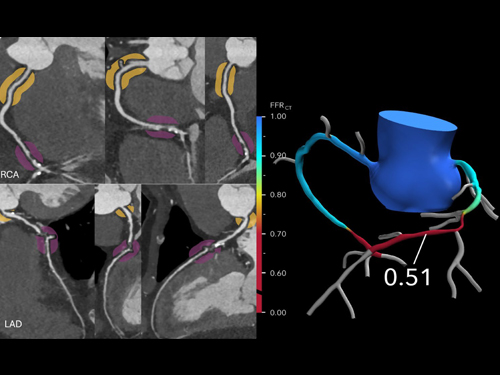

Advanced Coronary Imaging

Advanced coronary imaging utilizes cutting-edge technologies such as CT and MRI to non-invasively visualize the coronary arteries, assess heart structure, and detect plaque or blockages.